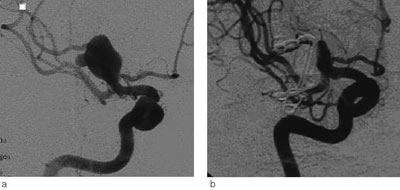

Universitetssykehuset er regionsykehus for vel 470 000 innbyggere i Helse Nord. Nevrokirurgisk avdeling har siden 1986 utført kirurgisk behandling av intrakraniale aneurismer (fig 1) (11). Endovaskulær behandling ble introdusert i 2000 (fig 2).

Behandlingsmetoden var avhengig av aneurismets lokalisasjon. Aneurismer utgående fra a. cerebri media ble vanligvis lukket med klipsligatur (43 av 46 tilfeller, 93 %), mens alle aneurismer i bakre kretsløp ble behandlet endovaskulært. For aneurismer utgående fra a. carotis interna og a. cerebri anterior var fordelingen av klipsligatur versus endovaskulær behandling henholdsvis 42 % versus 58 % og 58 % versus 42 %.